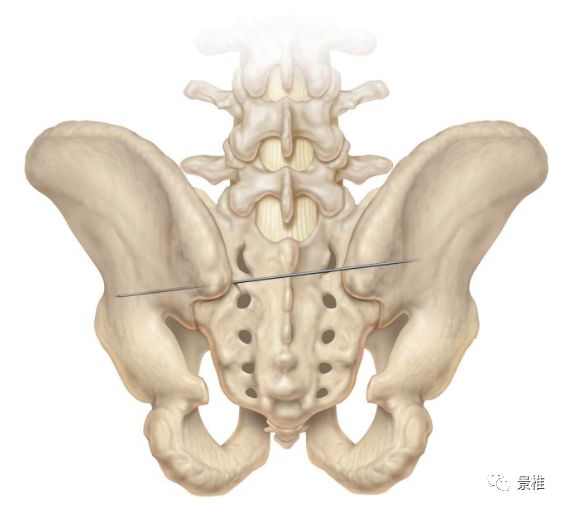

进针方向和水平面呈40°-50°夹角,和矢状面呈20°-30°夹角。

还有简便方法,那就是钉道朝向患者髂前下棘。俯卧位髂前下棘不好触及,摸大转子尖部也可以。开路锥指向同侧大转子尖端。